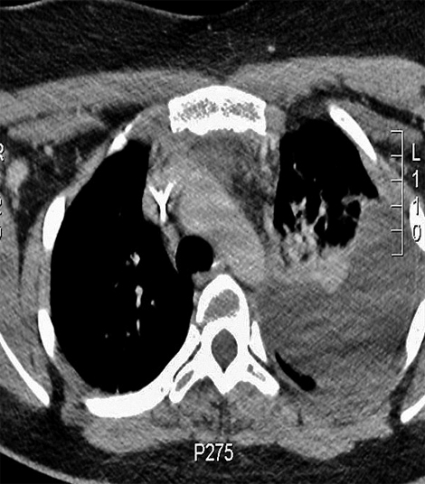

En tidigare helt frisk 20-årig kvinna insjuknade 1 vecka före ankomst med halsont, hög feber och bilateral smärta på halsen. Patienten beskrev vid ankomsten andningskorrelerade smärtor och tedde sig svårt septisk med CRP 344 mg/l och systoliskt blodtryck 70 mm Hg. Behandling med cefotaxim inleddes. Redan inom några timmar överfördes patienten till IVA, där hon lades i respirator med inotropt stöd. DT-undersökning av hals och torax visade utbredda infiltrat i lungor bilateralt, pleural vätska (Figur 2) och diffus svullnad till vänster på halsen.

Patienten erhöll pleuradrän på vänster sida, och antibiotikabehandlingen kompletterades med levofloxacin.